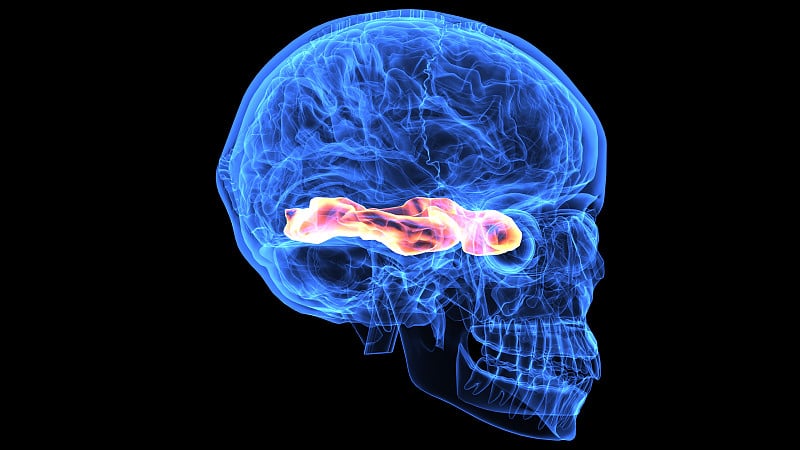

人体头部截面详情